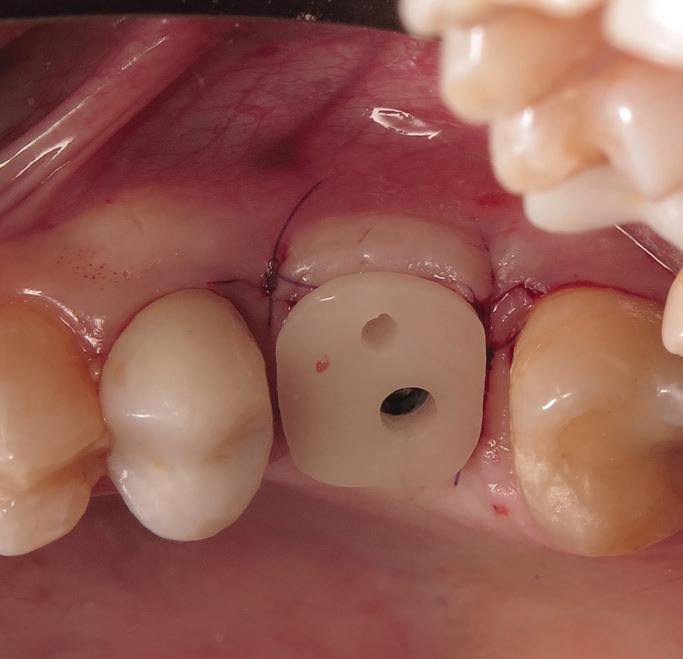

Tooth replacement from extraction to restoration. 3. Second-stage and impression procedures

The third part of this series reviews uncovering of implants that were buried in a 2-stage approach, provisionalization of the implant, and impression and scanning techniques.1 These techniques are all crucial for the final restorative outcome of the implant. The uncovering and second-stage procedures set the foundation for the shape and position of the soft tissue, which are very important esthetic factors. This information must also be properly transferred to the laboratory via a highly accurate impression so the laboratory has as much information as possible. If these steps are done properly, the result will be implant crowns that are easy to seat, biologically ideal, and esthetically pleasing.

Second-stage procedures